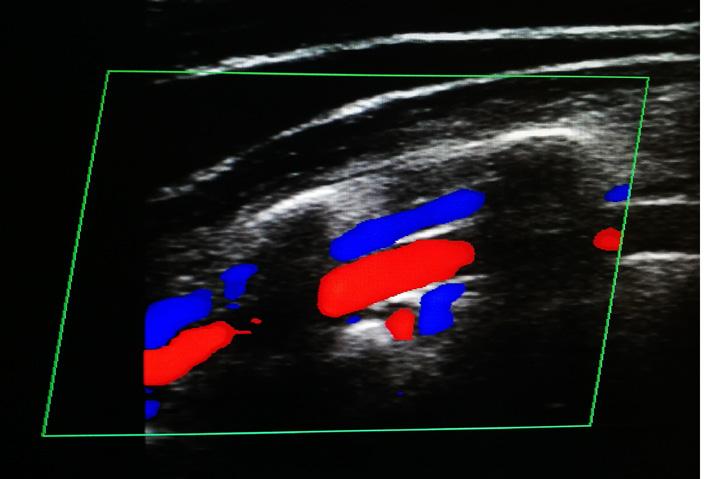

Duplex ultrasound uses conventional ultrasound combined with a Doppler beam. When ultrasound waves are reflected by moving objects such as blood, they experience a Doppler shift in frequency when returned to the transducer.3 In a colour Doppler image, frequencies are colour coded, so that flow towards the transducer appears a different colour to flow away from the transducer (see Image 1).3

Image 1. Colour Doppler ultrasonography. Red indicates motion towards the transducer, while blue indicates motion away.